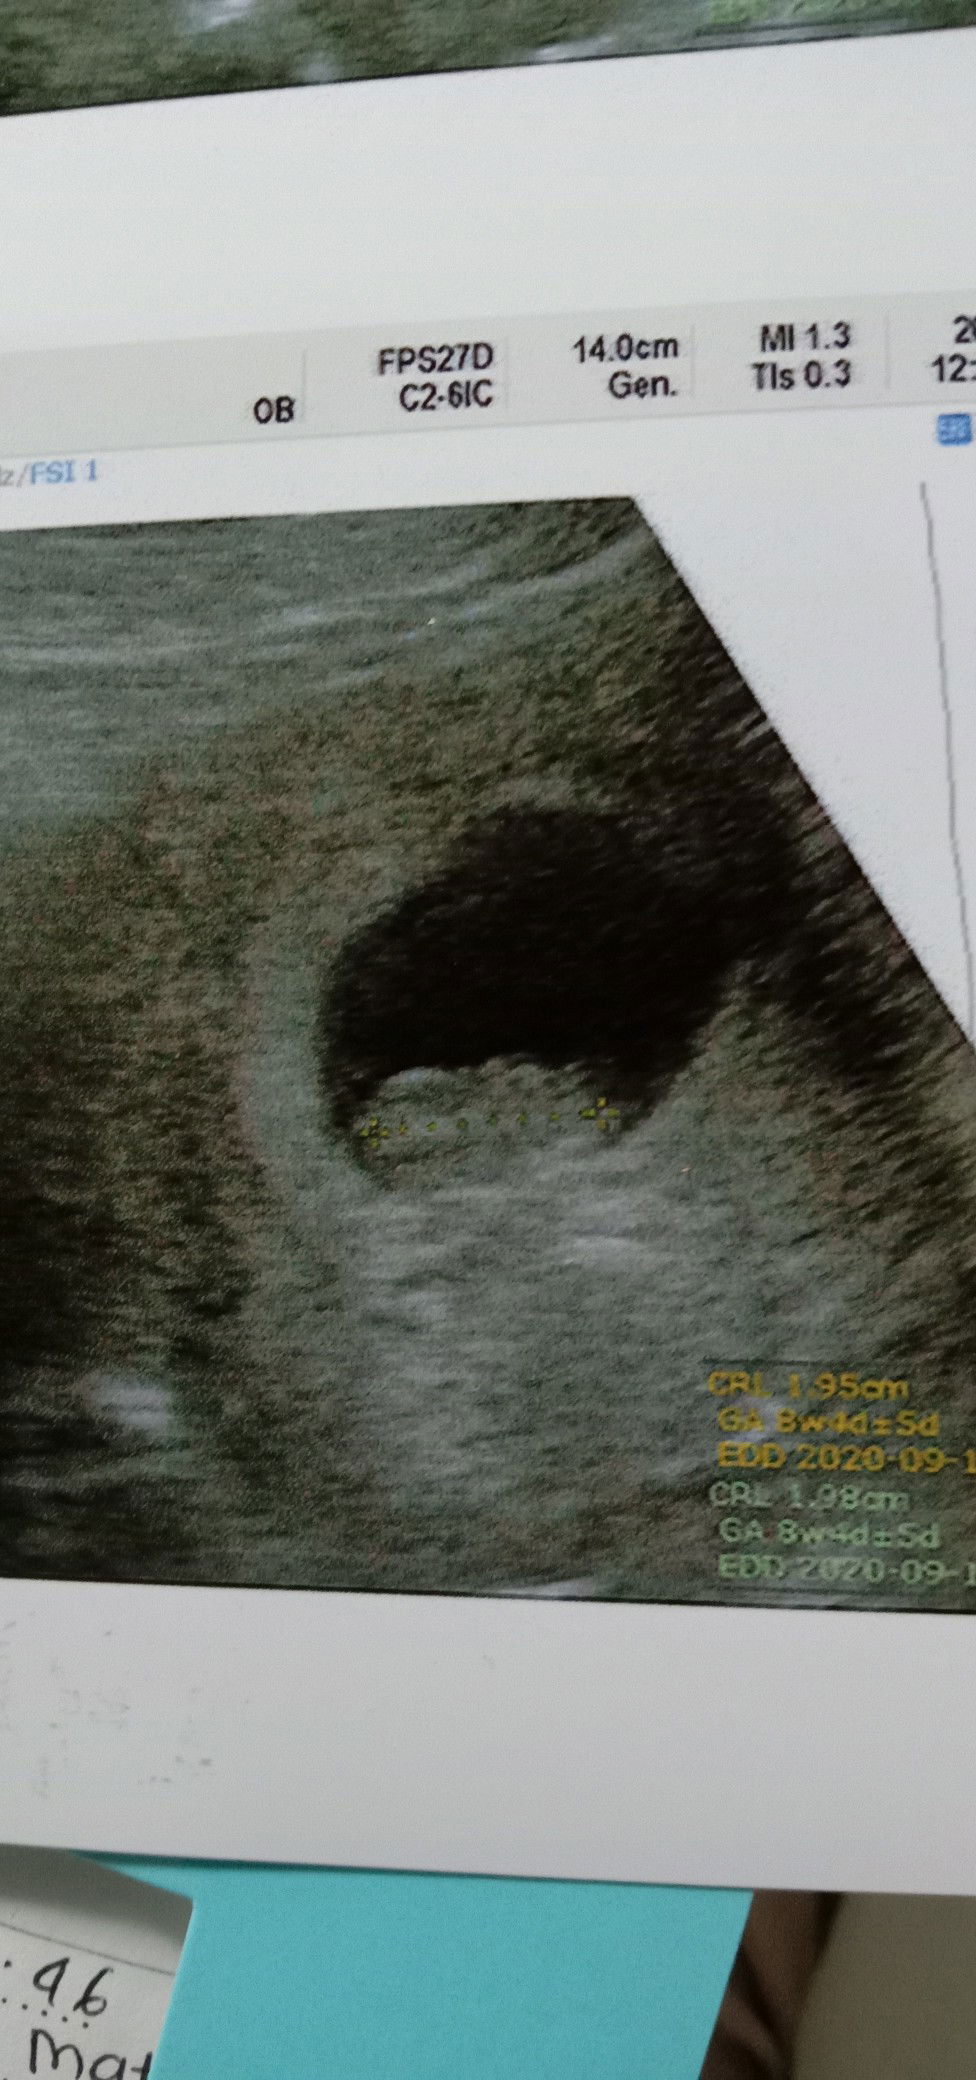

8week...

Alhamdulillah,...seneng bgt rasanya setelah USG yg kedua di TRI SEMESTER AWAL ini,janin sdh terlihat dan sdh ada detak jantungnya,meski hrs melewati mabok yg luar biasa rasanya,tp rasa HAPPY bisa mengobati semua itu...